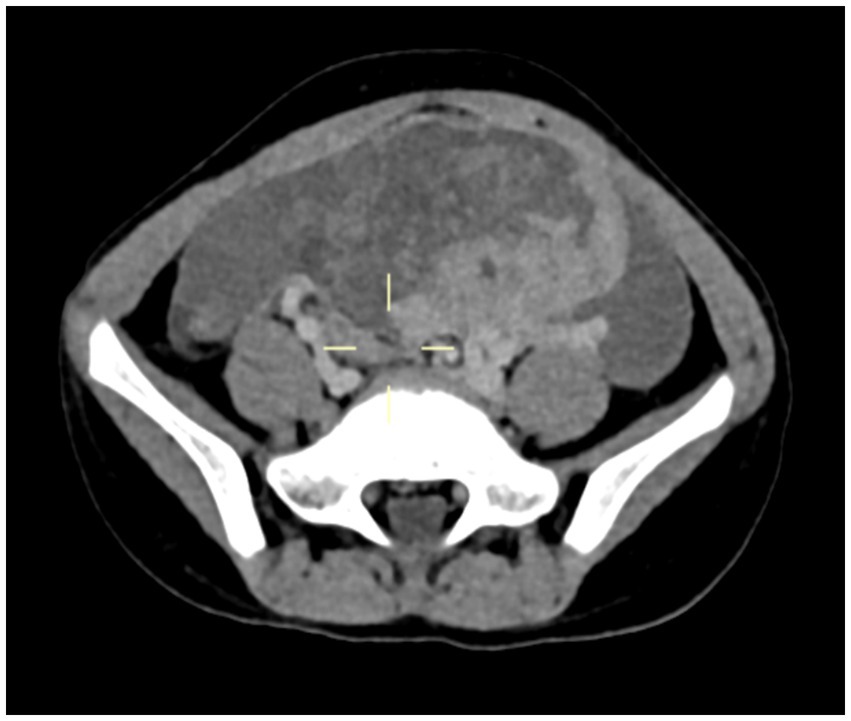

A 5-year-11-month-old girl was admitted to Wuhan Children’s Hospital (Wuhan Maternal and Child Healthcare Hospital) on 20 January 2022 due to paroxysmal periumbilical pain persisting for 4 days. On physical examination, there was positive tenderness in the lower abdomen, but there was no rebound pain or palpable mass. The levels of tumor markers CA125 and CA19-9 in serum were elevated, while serum carcinoembryonic antigen (CEA) and alpha-fetoprotein (AFP) levels were normal. The computed tomography (CT) scan showed a mixed-density mass shadow from the lower abdomen to the pelvic cavity, measuring 78 mm × 46 mm × 73 mm, with a CT value range of about 14–81 HU and unclear boundaries (Figure 1). An exploratory laparotomy was performed on 22 January 2022, which revealed peritoneal edema and tumor rupture originating from the left ovary. The bladder floor, omentum, small intestine, cecum, appendix, and anterior wall were covered with the ruptured tumor tissue and adhered tightly, making it difficult to separate. No abnormalities were found in the bilateral fallopian tubes and the contralateral ovary. A wide excision of the ovarian lesion, omentum, and peritoneum was performed along with appendectomy.

Figure 1

Computed tomography (CT) scan indicated a mixed-density mass shadow approximately 78 mm × 46 mm × 73 mm.